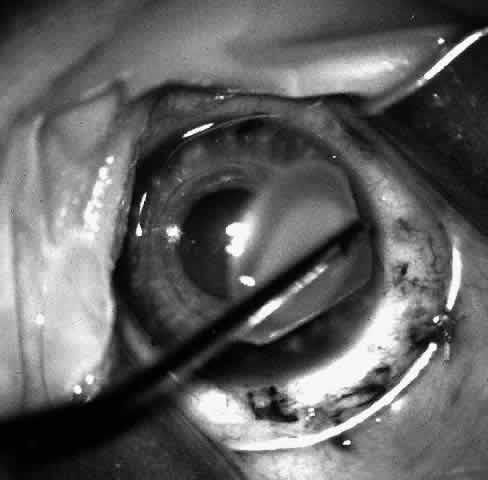

Children who have traumatic cataracts with corneal lacerations are well served by this procedure because the injury often destroys the capsular support that can be used to stabilize an intraocular lens.16–18 The epikeratophakia graft provides structural support for the weakened cornea and minimizes the induced irregular and regular astigmatism, in addition to correcting the optical error (Figs. 3 AND 4).

Fig. 3. Lacerated cornea with a hyphema. (Morgan KS, Ellis GS, Marvelli TL, Arffa RC: Epikeratophakia in children with traumatic cataracts. J Pediatr Ophthalmol Strabismus 23: 108–113, 1986)